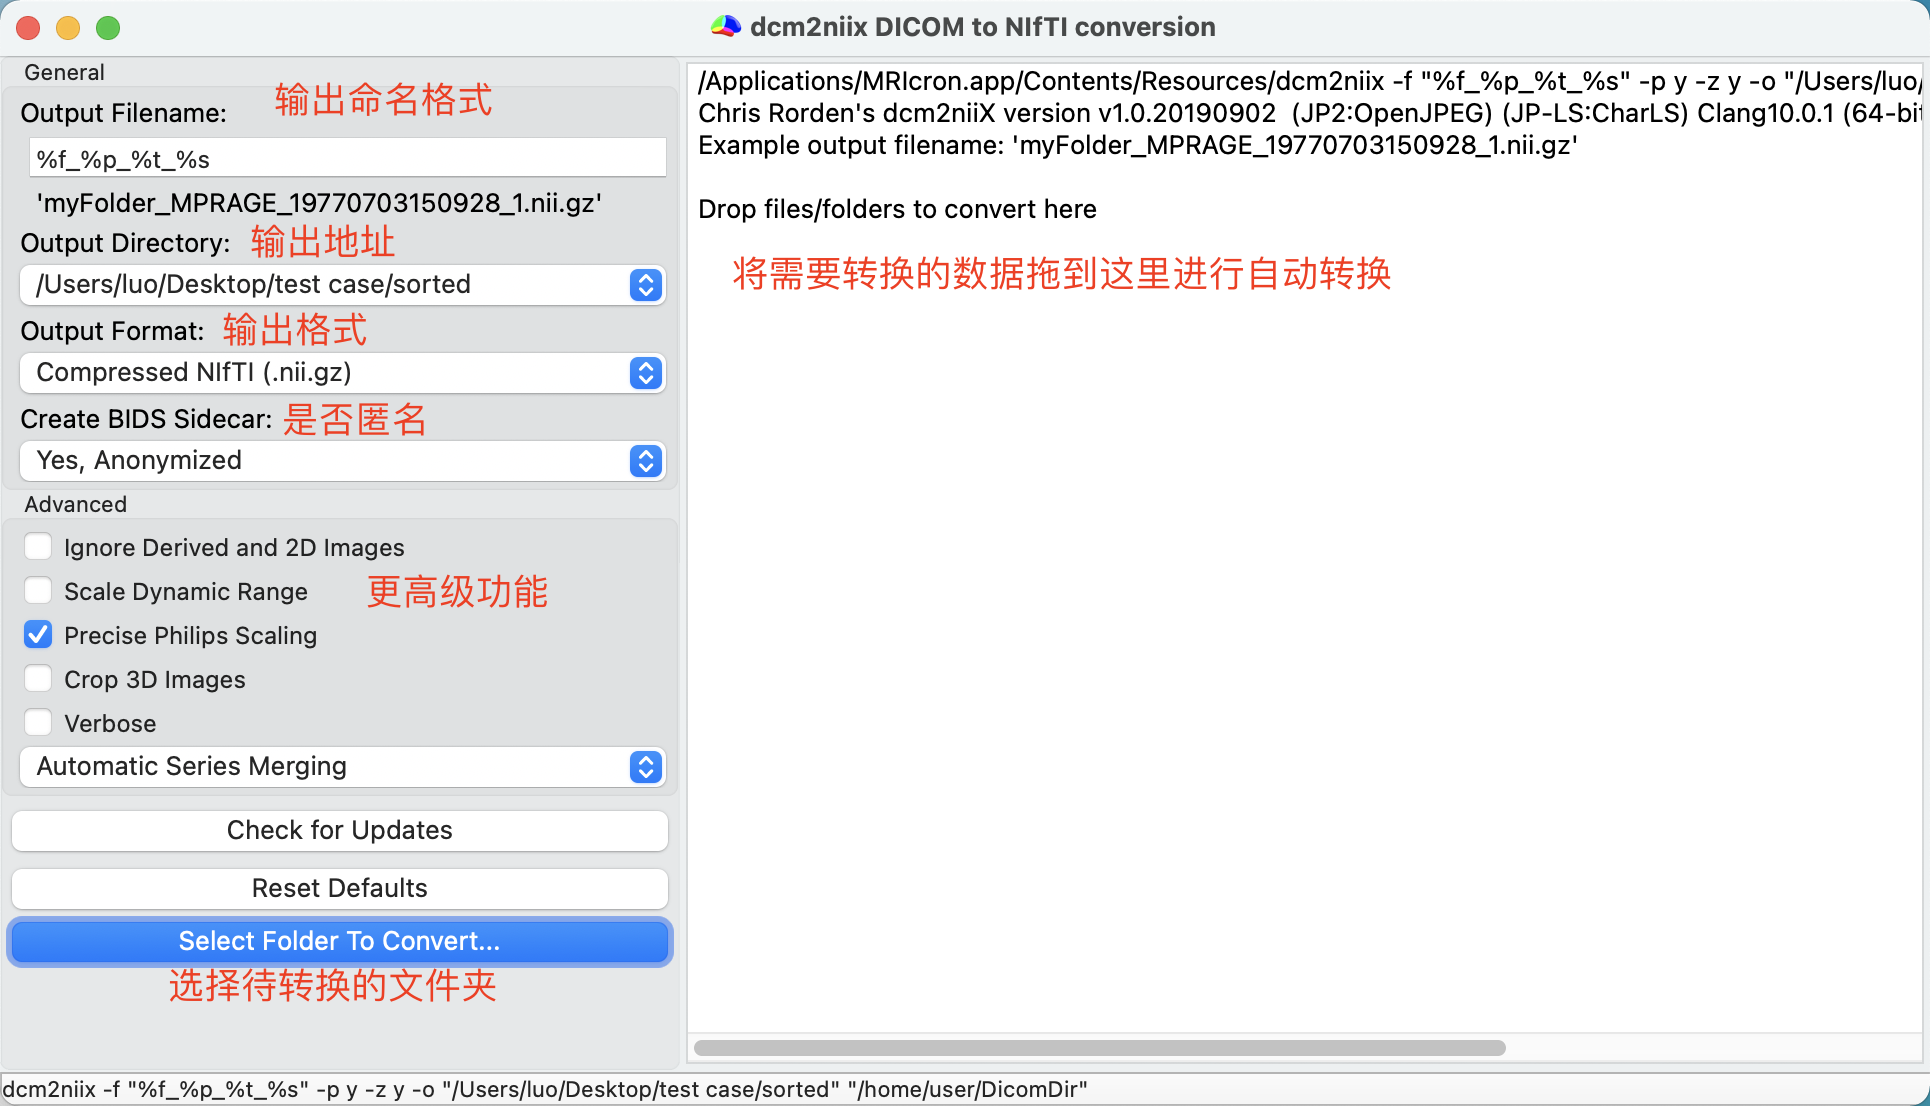

图形界面版需要先下载 MRICron。在上图左边设置好输出文件的命名格式,输出文件夹等参数,把dcm文件夹拖到右边空白处即可完成转换。

MRIcroGL包括一个简单的图形用户界面,用于控制dcm2niix。启动 MRIcroGL 后,选择 Import/ConvertDICOMtoNIfTI菜单项。

界面如下图所示。

复选框设置输出是压缩(创建.nii.gz文件)还是不压缩(创建.nii文件)。然后,您可以使用图片中描述的格式指定所需的输出文件名。

当您调整所需的输出名称时,软件将显示一个示例,说明您的文件将如何显示。您还可以选择是否要将输出保存到特定的文件夹中,或者是否应该在与输入DICOM文件相同的文件夹中创建NIfTI图像。

最后一步是拖放要转换为应用程序的文件夹。注意,界面总是以交互方式显示命令行,因此,当您通过选择复选框与界面交互时,您正在创建一个文本命令,您可以将其复制并粘贴到您喜欢的脚本中。